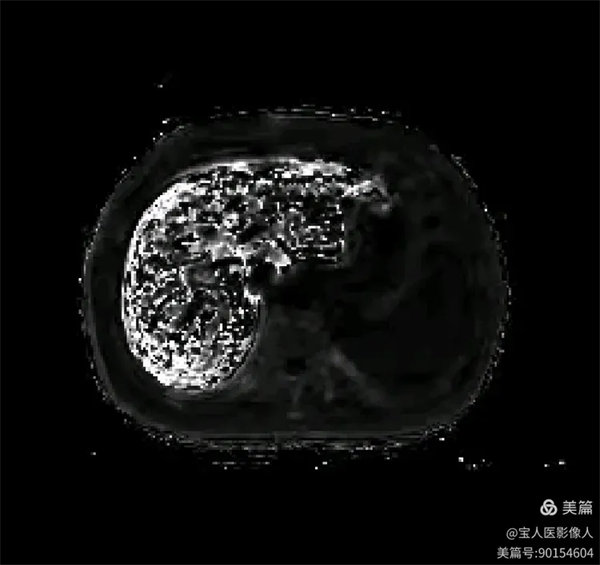

R2*圖,肝實質信號不均勻明顯升高。